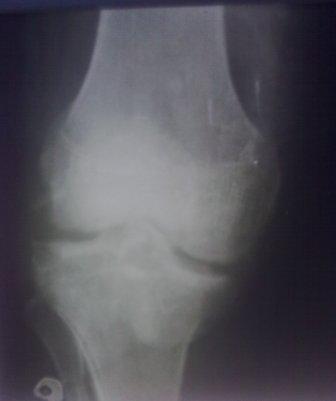

Здравствуйте уважаемые коллеги!Сегодня обратился больной 35л. Травму получил 3 мес.назад, упал в яму, лечился в отдаленном районе гипсовой повязкой, 1 месяц назад гипс сняли , и больной начал ходить с нагрузкой, постепенно появилась деформация коленного сустава, неустойчивость и боли. Локально: деформация коленного сустава, голень смещена кзади- типа подвывиха, разгибание 170гр. Сгибание 150гр.симптомов повреждение коллатеральных и крестообразных связок определить не удается из-за боли и контрактуры. Первичных снимков пока нет, обещали принести, имеется снимки через 2 месяца после травмы без гипса, недельной давности снимки в прямой проекции и К Т. Похоже, что импрессия переднемедиальной части внутреннего мыщелка б/берцовой кости, отрыв межмыщелкового возвышения.

Да, пока будем думать. Отправляю первичных снимков и фото ноги.

На снимке типичный перелом медиального тибиал плато с передним смещением (подвывих) по Schatzker IV. Консервативное лечение без медиальной опоры не может удержать деформирующие силы, и из-за вторичного смещения мыщелка конечность смещается в варус. Кроме передних смещений еще встречаются сложные фронтальные варианты переломов, и тогда голень подвывихивается кпереди.

А в данном случае мыщелок сросся со смещением кпереди и ротирован. За счет интактной наружной колонны опороспособность конечности сохранена, но остается варус и экстензия конечности. Для предоперационного расчета необходимо сделать на всю длину конечности рентгенограмму, а в остром периоде КТ и 3-мерный снимок помогут лучше ориентироваться в характере перелома.